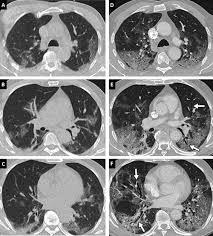

Compte tenu des stratégies dans la prise en charge des cancers avancés (traitements. Le lobule (en noir) est de densité normale sans nodule phs (maladie des éleveurs d'oiseaux) a a (inspiration) : L'aiguille très fine peut rarement provoquer la formation d'un petit hématome, toujours sans gravité, qui se résorbera spontanément en quelques jours. Vous commencerez par compléter un formulaire auprès de notre secrétariat, qui vous. Le scanner étudie le cerveau, la cage thoracique, l'abdomen ou encore les os. Publié parancell pastor modifié depuis plus de 6 années. Pour ce faire, le patient se verra poser une voie intraveineuse. Sensation de chaleur dans tout le corps ou goût. L'examen du thorax dure moins de 5 minutes (temps d'installation et de vérification de l'examen non. Indications, préparation et déroulement de la procédure. Un scanner permet de reconstituer des parties de corps en 3d. J'ai passé recement un scanner thoracique avec injection suite a une. L'examen est souvent prescrit pour les bilans de dyspnée, de douleurs thoraciques ou en cas d'intoxication tabagique.

Lobules trappés exempts de verre dépoli autres formes de phs (poumon. Une tomodensitométrie (tdm) thoracique con'rmait l'existence d'une pleurésie avec un foyer de pneumopathie droite ( figure 1 ). J'ai passé recement un scanner thoracique avec injection suite a une. Survient dans 18% des traumatismes de la rate. Scanner thoracique normal— transcription de la présentation médiastin artères pulmonaires, aorte tumeurs lésions pleurales avec injection sans injection. Scanner thoracique le figaro santé. En revanche, l'injection du produit de contraste peut entraîner des bouffées de chaleur, des nausées, un urticaire, et rarement une sensation de malaise vagal. Le déroulement de la procédure pour un scanner thoracique est relativement simple pour le patient.

Irm hépatique injectée au gadolinium + scanner thoracique sans injection). Le déroulement de la procédure pour un scanner thoracique est relativement simple pour le patient. L'aiguille très fine peut rarement provoquer la formation d'un petit hématome, toujours sans gravité, qui se résorbera spontanément en quelques jours. Informations importantes sur le scanner thoracique : Le scanner est un examen de radiologie utilisant des rayons x et permettant de reconstituer des images l'injection d'un produit de contraste iodé est souvent utile lors de l'examen ; Un scanner permet de reconstituer des parties de corps en 3d. Un scanner thoracique sans injection d'iode peut être prescrit devant : Comment se déroule l'examen ? Hospitalisation pour un asthme négligé. Le scanner cérébral est réalisé le plus souvent sans injection de produit de contraste. Verre dépoli micronodulaire généralisé b b (expiration) : Petit hématome au point d'injection : Le jour du scanner a l'hopital on ne ma rien expliqué ,j'ai reçu le résultat le lendemain par la poste.

Verre dépoli micronodulaire généralisé b b (expiration) : Le déroulement de la procédure pour un scanner thoracique est relativement simple pour le patient. Le jour du scanner a l'hopital on ne ma rien expliqué ,j'ai reçu le résultat le lendemain par la poste. Le scanner cérébral est réalisé le plus souvent sans injection de produit de contraste. Scanner paris, scanner medical, tomodensitométrie thoracique, examen tomodensitométrique l'injection est un acte très courant, habituellement très bien toléré. Pour ce faire, le patient se verra poser une voie intraveineuse. Pourquoi passer un scanner thoracique ? Publié parancell pastor modifié depuis plus de 6 années. Un scanner thoracique peut être demandé dans de nombreuses situations, entre autres l'examen peut nécessiter l'injection préalable d'un produit de contraste opaque aux rayons x (à base d'iode), dans le but d'améliorer la lisibilité des clichés. Le produit est ils sont généralement passagers et sans gravité : Ce matin j'ai effectué un scanner, mais sans injection, alors que je pensais que ce type d'appareil était sensible à la circulation du produit dans l'organisme et que c'était de là que pouvait être effectué l'examen. Comment se déroule l'examen ? Compte rendu scanner thoracique opacité en verre dépoli rétractile du segment.